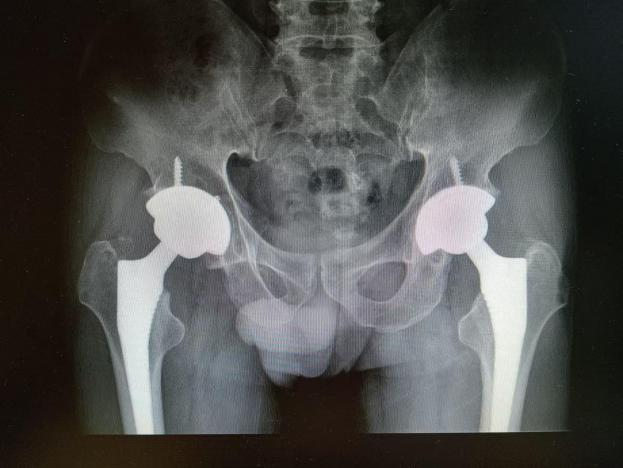

多年来,贵州航天医院各科室紧跟医学前沿,不断强技术、补短板,大力开展新技术、新项目,完成了许多高精尖、高难度、本地区“首例”的技术,填补了医院医疗技术空白,满足了群众日益增长的医疗需求。 贵州航天医院骨科率先在遵义地区开展骨搬移技术,截至目前,已治愈慢性骨髓炎、感染性骨不连、骨缺损、脉管炎、糖尿病足患者200余例,糖尿病足治疗保肢率达到98%。 本期,我们将为大家带来骨科特色技术——骨搬移技术(Ilizarov)。 案例分享 一名59岁的患者,身患糖尿病12年,在来我院3个月前出现了右脚溃烂的症状,来院就诊时,患者的右脚十分红肿,右脚脚趾坏死,伤口处不断流出黑红色脓液,情况十分严重。在接诊到患者时,骨科专家团队高度重视,立刻为患者完善了CT血管造影(CTA)等相关检查,诊断为:2型糖尿病,糖尿病周围血管病变,右糖尿病足。 术 前 考虑到患者情况比较严重,为最大限度保证患者肢体完整,科室专家团队进行了严格的讨论评估,为患者制定了骨搬移技术治疗方案,在征得患者及其家属的同意后,成功通过搬移骨块为患者进行治疗,促进患者病变肢体血管再生。 胫骨横向骨搬移外架固定 清除感染病灶 术后调节外架,通过搬移骨块 促进患肢血管再生 患者在术后三周前来换药,观察到感染得到进一步控制;术后六周复查,患者病变处已愈合,进行CT血管造影(CTA)后可明显观察到足部血管再生。 术后3周 术后6周愈合 CT血管造影见足部血管再生 糖尿病患者全身与局部的问题互为影响,形成恶性循环,糖尿病足溃疡创面迁延不愈,常见干性坏疽、湿性坏疽、趾坏死、深且大的溃疡以及骨髓炎等症状,还可导致脓毒血症,以往为保全生命,患者被迫选择一次或多次截肢。骨搬移技术的发展进步,能在血糖有效控制、局部有效清创下,有效促进患肢微血管再生,改善患肢血供,达到糖尿病足更快治疗康复的目的,并能根据病变情况最大限度的保障患者肢体完整。 什么是骨搬移技术 骨搬移技术是通过使用专用的骨外固定器固定骨段,每天缓慢牵拉,在牵拉搬移过程中,骨段尾部形成新骨及新的软组织,从而修复骨骼缺损及软组织缺损。是治疗大段骨缺损、骨不连、骨感染、肢体畸形的金标准方法,也用于治疗脉管炎、糖尿病足等肢体缺血性疾病。 骨感染缺损 切除感染段 搬移骨段 新骨形成 骨感染根治愈合 骨搬移技术原理 生物组织在持续、稳定、缓慢牵拉下,能刺激细胞分裂、组织再生,骨外固定技术运用该原理,通过持续缓慢调节外固定器形成牵拉张力,促进牵引成骨与相邻组织再生,如神经、血管、肌肉、皮肤等再生,达到治疗大段骨缺损、肢体缺血如糖尿病足等疾病的目的。 骨搬移技术优势 (一)除治疗骨缺损、骨不连外,有更广的适用范围,利用组织再生、血管再生等特性,能大量运用于肢体畸形的矫形、糖尿病足等的治疗。 (二)治疗效果确切,重建肢体外型和功能,极大降低截肢率和残疾率。 (三)明显提高了患者生活质量,极大减轻其家庭及社会负担。 肢体畸形的矫形 慢性骨髓炎 骨段切除 术后1年 濒临截肢的脉管炎术后6周 难愈创面术后3周 贵州航天医院骨科 专家团队 赵学平 骨科主任 主任医师 临床擅长:从事骨科临床工作30余年,对骨科常见疾病的诊治具有丰富的临床经验。 世界中医药联合会脊柱康复专业委员会常务理事,中华中医药学会整脊分会常务委员,中国中西医结合学会骨伤科分会肢体矫形功能重建与康复专家委员会常务委员,中国研究性医院学会骨科创新与转换专业委员会关节外科学组保髋工作委员会常委,中国康复技术转化及发展促进会骨外科与康复技术转化专业委员会常务委员,泛珠三角区域运动医学联盟(PPRD-SMA)理事会常务理事,中国研究型医院学会运动医学专业委员会委员,贵州省中医药学会整脊分会副主任委员,贵州省中西医结合学会银质针专业委员会副主任委员,贵州省康复医学会骨与关节专业委员会常务委员,贵州省人民医院骨科专科联盟常务理事,贵州省康复医学会骨内科专业委员会常务委员,中华医学会贵州省骨科学会委员,贵州省康复医学会脊柱脊髓专业委员会常务委员,贵州省运动医学分会委员,贵州省康复医学会骨与软组织肿瘤专业委员会委员,遵义市医学会创伤分会副主任委员,贵州省康复医学会骨内科专业委员会遵义地区分会常务委员,遵义市医疗事故鉴定、伤残鉴定、工伤鉴定、司法鉴定专家。 长期从事骨科临床研究及教学工作,在国家级、省部级杂志发表论文20余篇,SCI论文2篇,参与主编骨科专著2部,主持省部级科研项目2项,参与指导省部级、市级科研项目6项。 陈明勇 骨科副主任 副主任医师 临床擅长:从事创伤骨科工作约20年,对骨缺损、骨不连、骨肿瘤、肢体畸形等的肢体矫形重建及功能重建,慢性化脓性骨髓炎的根治治疗、糖尿病足的保肢治疗、快速康复理念(ERAS)下的老年骨折的诊治,四肢复杂骨折的诊治,四肢骨折等微创手术治疗具有丰富的临床经验。 2004年毕业于遵义医学院临床专业,曾在中国人民解放军总医院、广西医科大学第一附属医院、上海第六人民医院骨科进修。中国中西医结合学会骨伤科专业委员会横向骨搬移治疗糖尿病足及微血管网再生学组首届委员,遵义市医学会创伤分会常务委员。 瞿 辉 骨科 副主任医师 临床擅长:对骨科的常见病、关节外科、脊柱外科及运动医学疾病的诊治具有丰富的临床经验,熟练掌握骨科手术操作技术。 毕业于遵义医学院临床医学系,2005年前往广州中山大学第一附院骨显微医学部进修学习,2011年前往成都华西医院进修学习,并多次在省内外学习骨科相关知识,是中华医学会骨科分会会员。 赵兴东 骨科 主任医师 临床擅长:擅长骨科的常见病及各种创伤、四肢骨折创伤修复、骨感染、手足疾病的诊治和手足体表畸形的矫形整复,熟练掌握骨科四肢骨病及创伤的手术操作技术,尤其在四肢关节复杂性损伤、手足外伤、组织缺损创面、难治创面的皮瓣修复方面及平足、高弓足矫形方面及四肢慢性疼痛诊治、康复方面具有丰富的临床经验。 硕士研究生,毕业于遵义医学院临床外科系,2015年前往山东省立医院手足外科进修学习;遵义市医学分会创伤分会第一、二届委员,遵义市手外科医学会第二委届员会常务委员;在省级及省级以上期刊发表文章9篇,参编著作2部,参与主持并完成市级课题1项,参与市级课题2项、省级课题1项。 张俊凯 骨科 副主任医师 临床擅长:从事骨科临床工作28年,对创伤骨折、骨感染、骨缺损、骨不连等外科诊治,四肢骨折的微创手术治疗,四肢复杂骨折(如关节内粉碎性骨折、多发骨折等)的损伤控制及手术治疗等具有丰富的临床经验。 1995年毕业于遵义医学院临床专业,2009年前往复旦大学附属医院骨科进修1年。 卢懿明 骨科 副主任医师 临床擅长:从事骨科工作18年,对创伤骨折、四肢骨折的微创手术治疗、四肢复杂骨折(如关节内粉碎性骨折、多发骨折等)的损伤控制及手术治疗,尤其是髋部骨折的PFNA等微创技术,踝关节骨折、膝关节周围骨折的Mipo微创技术等具有丰富的临床经验,开展了4项新技术,发明6项新型专利技术。 2005年毕业于遵义医学院临床专业,2017年,前往南方医科大学第三附属医院骨科进修半年,回院后运用Mipo技术对骨干骨折及干骺端骨折的治疗技术,同时积极开展骨盆骨折、髋臼骨折腹直肌外侧切口的应用;发表了多篇专业论文,经常参与省内外学术交流会授课,获得医院荣誉称号多个。 邬夏荣 骨科 副主任医师 临床擅长:从事骨科工作16年,对四肢复杂骨折、骨肿瘤的诊治,尤其是足踝创伤、慢性踝关节损伤、平足症等诊疗具有丰富的临床经验。 2006年毕业于遵义医科大学临床医学专业,曾在陆军军医大学西南医院进修学习,发表多篇骨科学术论文。 余德怀 骨科 副主任医师 临床擅长:从事骨科工作10余年,对运动医学、骨关节、脊柱外科常见病、多发病的诊治具有丰富的临床经验。 硕士研究生,2011年毕业于遵义医学院临床医学专业,曾前往遵义医科大学附属医院运动医学专业进修学习;是贵州省医学会运动医学分会青年委员,西部关节镜联盟委员;发表多篇骨科学术论文。 冯 乾 骨科 副主任医师 临床擅长:从事骨科工作近20年,熟练掌握骨科多发病及常见病的诊治,尤其对脊柱退变性疾病的诊断及治疗具有丰富的临床经验,主要研究脊柱微创相关治疗方式,能熟练开展椎间孔镜及VBE。 曾前往北京大学第三医院进修学习疼痛及椎间孔镜、首都医科大学友谊医院专业进修脊柱内镜;是贵州省康复医学会第三届脊柱脊髓专业委员会委员;发明专利3项、发表脊柱外科专业论文多篇。 张艳金 骨科 副主任医师 临床擅长:从事骨外科工作16年,对复合伤、多发伤的救治、四肢骨干骨折、关节周围骨折、骨肿瘤、骨髓炎等诊治具有丰富的临床经验。 中共党员,硕士研究生,2006年本科毕业于山西医科大学第二临床医学院,2011年研究生毕业于北京军区总医院;在“老年COPD患者合并髋部骨折的诊治”国际合作课题组研究两年,在老年髋部骨折的诊治方面具有丰富的经验,并发表论文6篇;承担遵义市级课题1项;承担遵义医科大学的临床教学工作,获得遵义医科大学优秀带教老师荣誉。编撰有《骨科疾病诊疗精粹》一书,开展2项新技术,编撰地方规范《务川自治县创伤骨科常见疾病诊疗规范》一书。 赵小锋 骨科 副主任医师 临床擅长:从事骨科临床工作11年,对骨科常见病、多发病诊疗有较为丰富的临床经验,擅长脊柱相关疾病诊断及治疗,尤其是颈、腰、腿疼痛疾病诊断及治疗,擅长胸腰椎骨折微创经皮穿刺内固定术、经皮穿刺椎体成形术、经皮穿刺脊柱内镜下腰椎间盘摘除术、单纯开创腰椎间盘摘除术、腰椎滑脱复位椎间植骨椎融合内固定术、腰椎管狭窄减压融合内固定术及人工髋、膝关节置换术等。 2012年毕业于遵义医学院外科学专业硕士研究生,2019年参加“遵义市115医学人才精英计划”于上海交通大学第一附属医院培训学习,2023年于北京大学第三人民医院脊柱外科进修学习,曾获得遵义市优秀医师荣誉称号。 遵义市手外科第一届委员,遵义市医学会创伤分会第一届委员,遵义市医学会创伤分会第二届委员,贵州省康复医学会第三届脊柱脊髓专业会委员,遵义市医学会烧伤与整形外科学分会委员,发表论文5篇,其中国家级核心期刊1篇,SCI论文1篇,主持市级课题1项并结题,参与市级课题2项。 贵州航天医院骨科简介 基本情况 贵州航天医院(原3417医院)骨科组建于1968年,前身是以创伤和断肢(断指)再植闻名于世的上海市第六人民医院骨科,中国断肢(断指)再植的奠基者、中科院院士陈仲伟等著名专家、学者多次莅临科室指导医疗、教,是贵州省最早拥有专业骨科技术科室之一,在70年代开展了贵州省首例断肢(断指)再植手术。组建50余年来,诊治患者已逾百万,挽救了无数的伤病员,成为了保障遵义地区人民群众健康的重要支撑。 经过几代人的不懈努力,今天的骨科,已由创伤骨科发展至骨病、骨肿瘤、骨结核等领域,现有脊柱外科、关节外科、四肢创伤、手足外科四个亚专科,成为了集医疗、教学、科研于一体的综合学科,是贵州省临床重点专科、遵义市临床重点专科、遵义市骨科临床医学中心、遵义市基层骨科专科联盟理事长单位。 科室目前开放床位110张,共有医护人员50余人,副高级以上专家18人,硕士研究生15人。拥有一流骨科医疗设备多台,每年不定期选派优秀技术骨干到全国各大知名医学院校进修、学习、参观、交流,并邀请国内、国外知名专家教授来院进行交流、指导,通过不断引进国内外先进的诊疗技术,科室医疗技术水平稳步提升,为广大人民群众提供了优质的医疗服务。 专科特色 骨一科 (一)骨缺损、骨不连的肢体与功能重建 胫骨横向骨搬移技术治疗糖尿病足: (二)慢性骨髓炎的根治治疗 (三)肢体缺血性疾病如糖尿病足、脉管炎的保肢治疗 (四)皮瓣修复 (五)复杂创伤的治疗 (六)老年髋部骨折及小儿骨折快速手术 老年髋部骨折: 骨二科 (一)胸腰椎骨折微创经皮椎弓根螺钉固定术 (二)老年性骨质疏松性患者腰椎滑脱脊柱内固定术(骨水泥螺钉) (三)V形双通道脊柱内镜技术(VBE)腰椎融合术治疗腰椎退行性疾病 (四)老年性骨质疏松性骨折(PVP/PKP)术 (五)人工髋关节置换术 (六)双侧股骨头坏死人工全髋关节置换 (七)右侧全髋置换术后假体周围骨折翻修 (八)人工膝关节置换术 (九)人工膝关节假体松动翻修 (十)关节镜技术 传统手术切口 关节镜技术切口 诊疗范围 骨一科 1.四肢创伤、矫形。 2.手、足踝外科。 骨二科